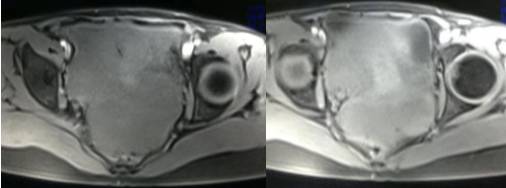

女性,42岁。

主诉:下腹部胀痛不适1月余

病史:自诉13岁时患“结核”,8年前行“左侧附件包块”切除术。

病理结果:黄体血肿

根据时间不同MR信号也有所不同,TIWI脂肪抑制序列可以鉴别脂肪和出血。

卵巢囊肿:呈均匀的T1WI 低信号,T2WI 高信号,边界清楚,壁薄,大多数病灶直径≤5 cm,但囊肿的起源及定性诊断困难。

功能性囊肿:因囊肿内容物成分不同,信号可有改变,随访观察数月后其信号和大小可出现变化或消失。